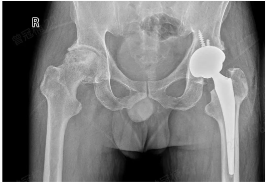

上个月,张大哥来探望刚出生的小侄子,在医院,他看到成人ai 副院长、郑州市中心医院副院长杨德金讲解的股骨头坏死的科普宣传短片。用人工制造的髋关节来替代“坏掉的”髋关节,并且随着现代关节置换技术的改进,人工关节假体的磨损率、松动率、感染率等均有大幅度下降,能大大改善关节运动的功能,尽早回归正常生活。

手术!先行左侧人工全髋置换术,术中杨德金院长仔细分离、剥离手术瘢痕、松解粘连,凿除之前硬化的人工骨,开通髓腔,整个手术过程一气呵成。术后第二天,在杨德金院长的指导下张大哥拄着双拐下床,深深呼吸一口,坚定地迈开第一步......

杨德金提醒:随着社会发展,酒精性股骨头坏死的发病人群不断增多,长期大量喝酒就是非常重要的诱因,一定要戒酒!酒精性股骨头坏死首先需要明确股骨头坏死的程度,进行阶梯式治疗,如果是1~2期股骨头坏死,可以进行保髋治疗,发现及时的3期早期部分病人也可以考虑定制化的部分关节置换术来保关节治疗,3期晚期或者4期股骨头坏死患者,则建议进行人工髋关节置换术治疗。